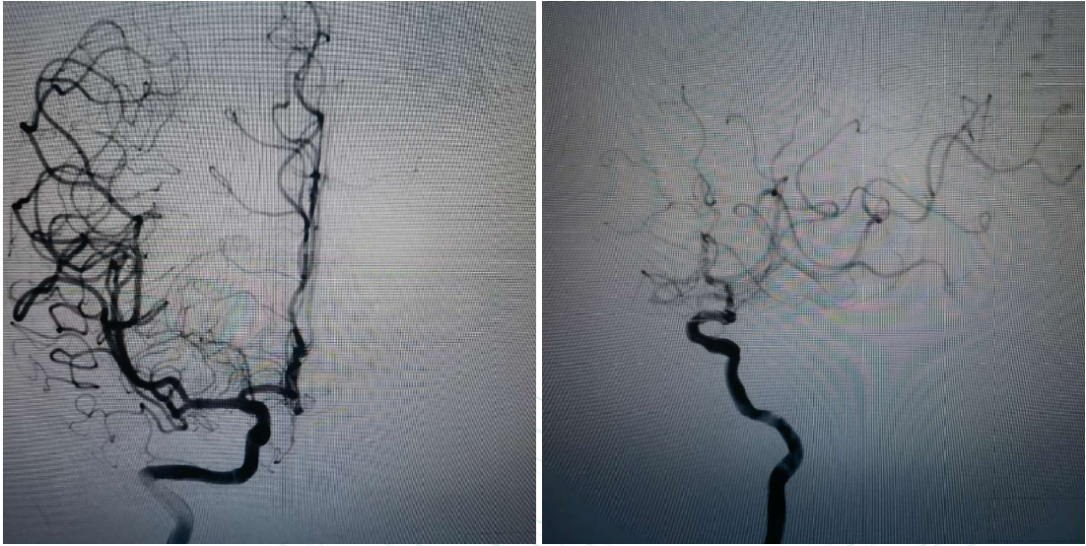

Preoperative Angiography

Right internal carotid angiography showed occlusion of the right ICA, with no collateral circulation in the right ACA or right MCA, and no compensatory blood flow in the surrounding area.